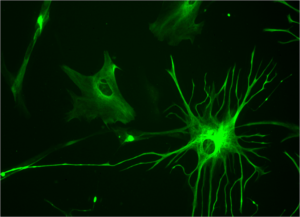

آستروسیتها سلول‌های مغزی ستاره ای شکل غیر نورونی هستند که نقش آنها در پشتیبانی‌ و حفظ سلامت نورونها شناخته شده است.

تحقیقی که انجام شده است اهمیت این سلولها را در شکلگیری صحیح مدارهای عصبی و زنده نگاه داشتن نورونها آشکار می‌سازد.

در این تحقیق دریافته اند که نوع خاصی‌ از آستروسیتهای نخاعی، پروتئینی به نام Sema3a را به میزان زیادی تولید می کنند.

عدم وجود این پروتئین منجر به عدم تشکیل ارتباطات صحیح بین نورونهای حرکتی و مرگ نیمی از این نورونها شده، می تواند منجر به بیماری ALS شود.